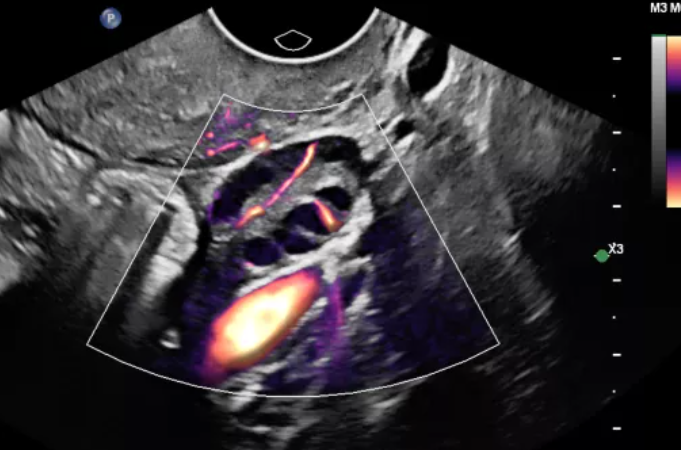

- STIC – визуализация плода в динамике;

CPA дуги аорты плода с Flow Viewer

ЦДК сердца плода, четыре камеры, с Flow Viewer

CPA плаценты с Flow Viewer

Автоматическое сканирование

ЦДК перфузии легких плода с Flow Viewer